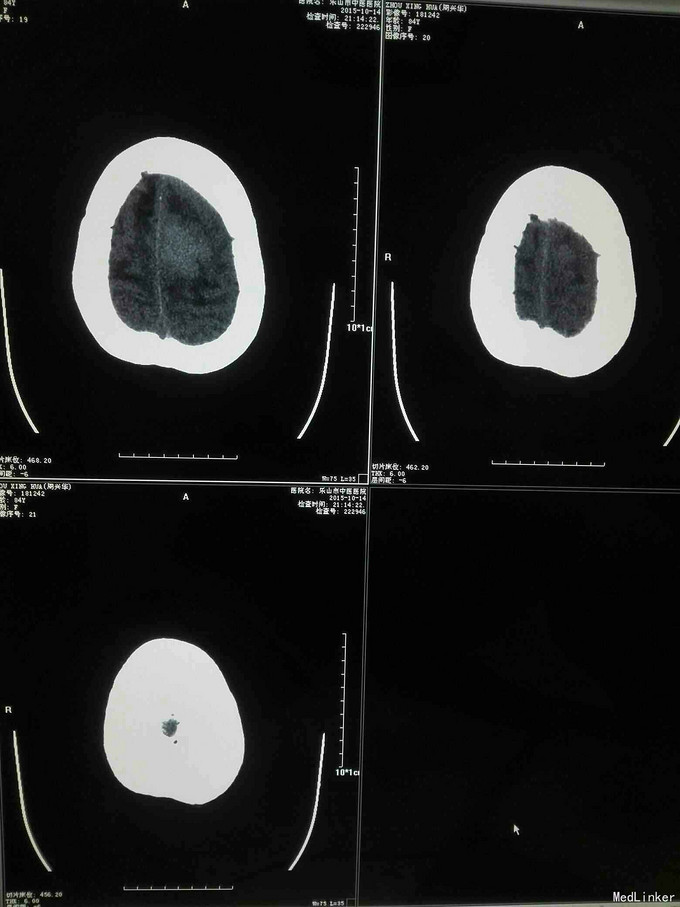

急诊CT病例

昏迷不醒就诊